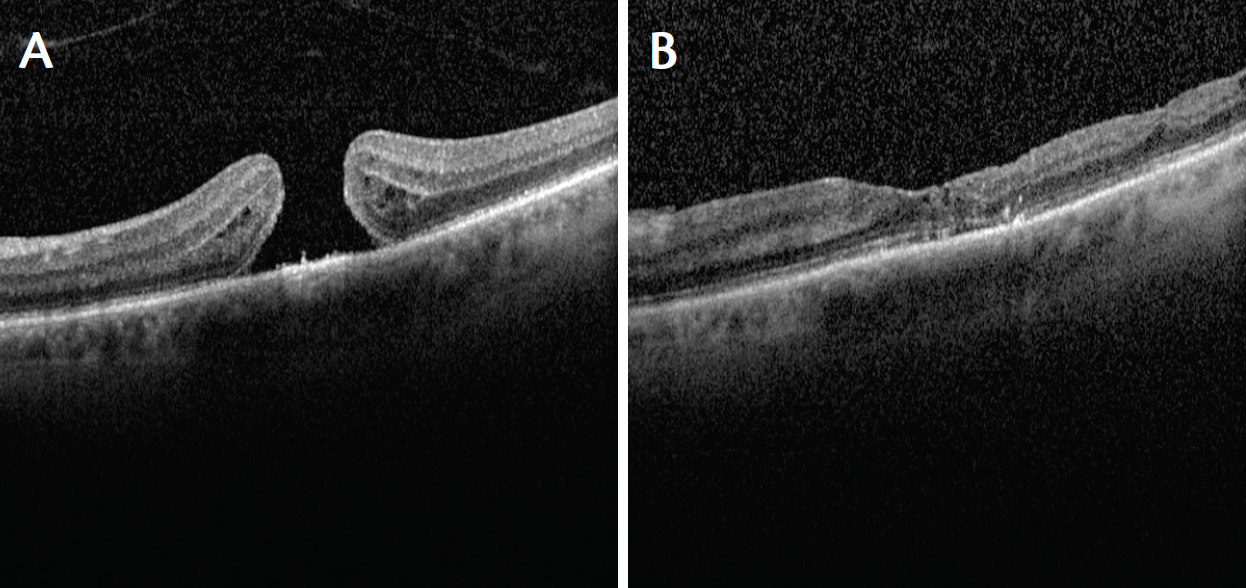

A 68-year-old woman presented with a macular hole of 1 month’s duration. Her visual acuity in the affected eye was 20/80, and the hole was slightly more than 400 µm in width (Figure 1A). She underwent vitrectomy with an ILM flap folded over the hole. At 3 months after surgery, the macular hole was closed, a small ellipsoid zone defect was present, and the patient’s visual acuity was 20/30 (Figure 1B).

Figure 1. Case No. 1: Macular hole of 1 month’s duration with diameter of slightly more than 400 μm (A). Visual acuity 20/80. Patient underwent vitrectomy with ILM flap folded over the hole. At 3 months after surgery, the macular hole was closed, a small ellipsoid zone defect was present, and visual acuity was 20/30 (B).